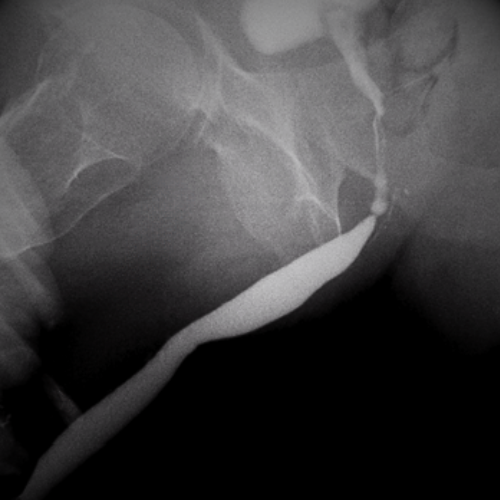

- Fase retrógrada: Se apoyará el pico de una jeringa en el meato uretral (el orificio por donde sale la orina) y se introducirá contraste por la uretra desde allí. Este líquido es una sustancia que hace que su uretra sea perfectamente visible en las imágenes de rayos X. Es posible que el personal médico necesite mover o estirar suavemente el pene para colocarlo en la posición correcta y le pedirán que avise si siente alguna molestia. Esta fase también se conoce como uretrocistografía retrógrada.

- Fase miccional: A continuación se coloca una sonda muy delgada a través de la uretra para llenar la vejiga con contraste. Una vez que se tienen suficientes ganas de orinar, se retira la sonda y se da la orden para miccionar. Al mismo tiempo se vuelven a tomar imágenes en diferentes ángulos con un equipo de rayos X. Esta fase también se conoce como cistouretrografía miccional seriada.

- Muestra la uretra en acción: no solo su forma estática, sino cómo se comporta durante la micción. Es un estudio «en tiempo real».

- Detecta estenosis (estrecheces) con exactitud: permite medir su longitud, ubicación y severidad —datos esenciales para planificar una cirugía.

- Identifica fugas urinarias tras un trauma o cirugía.